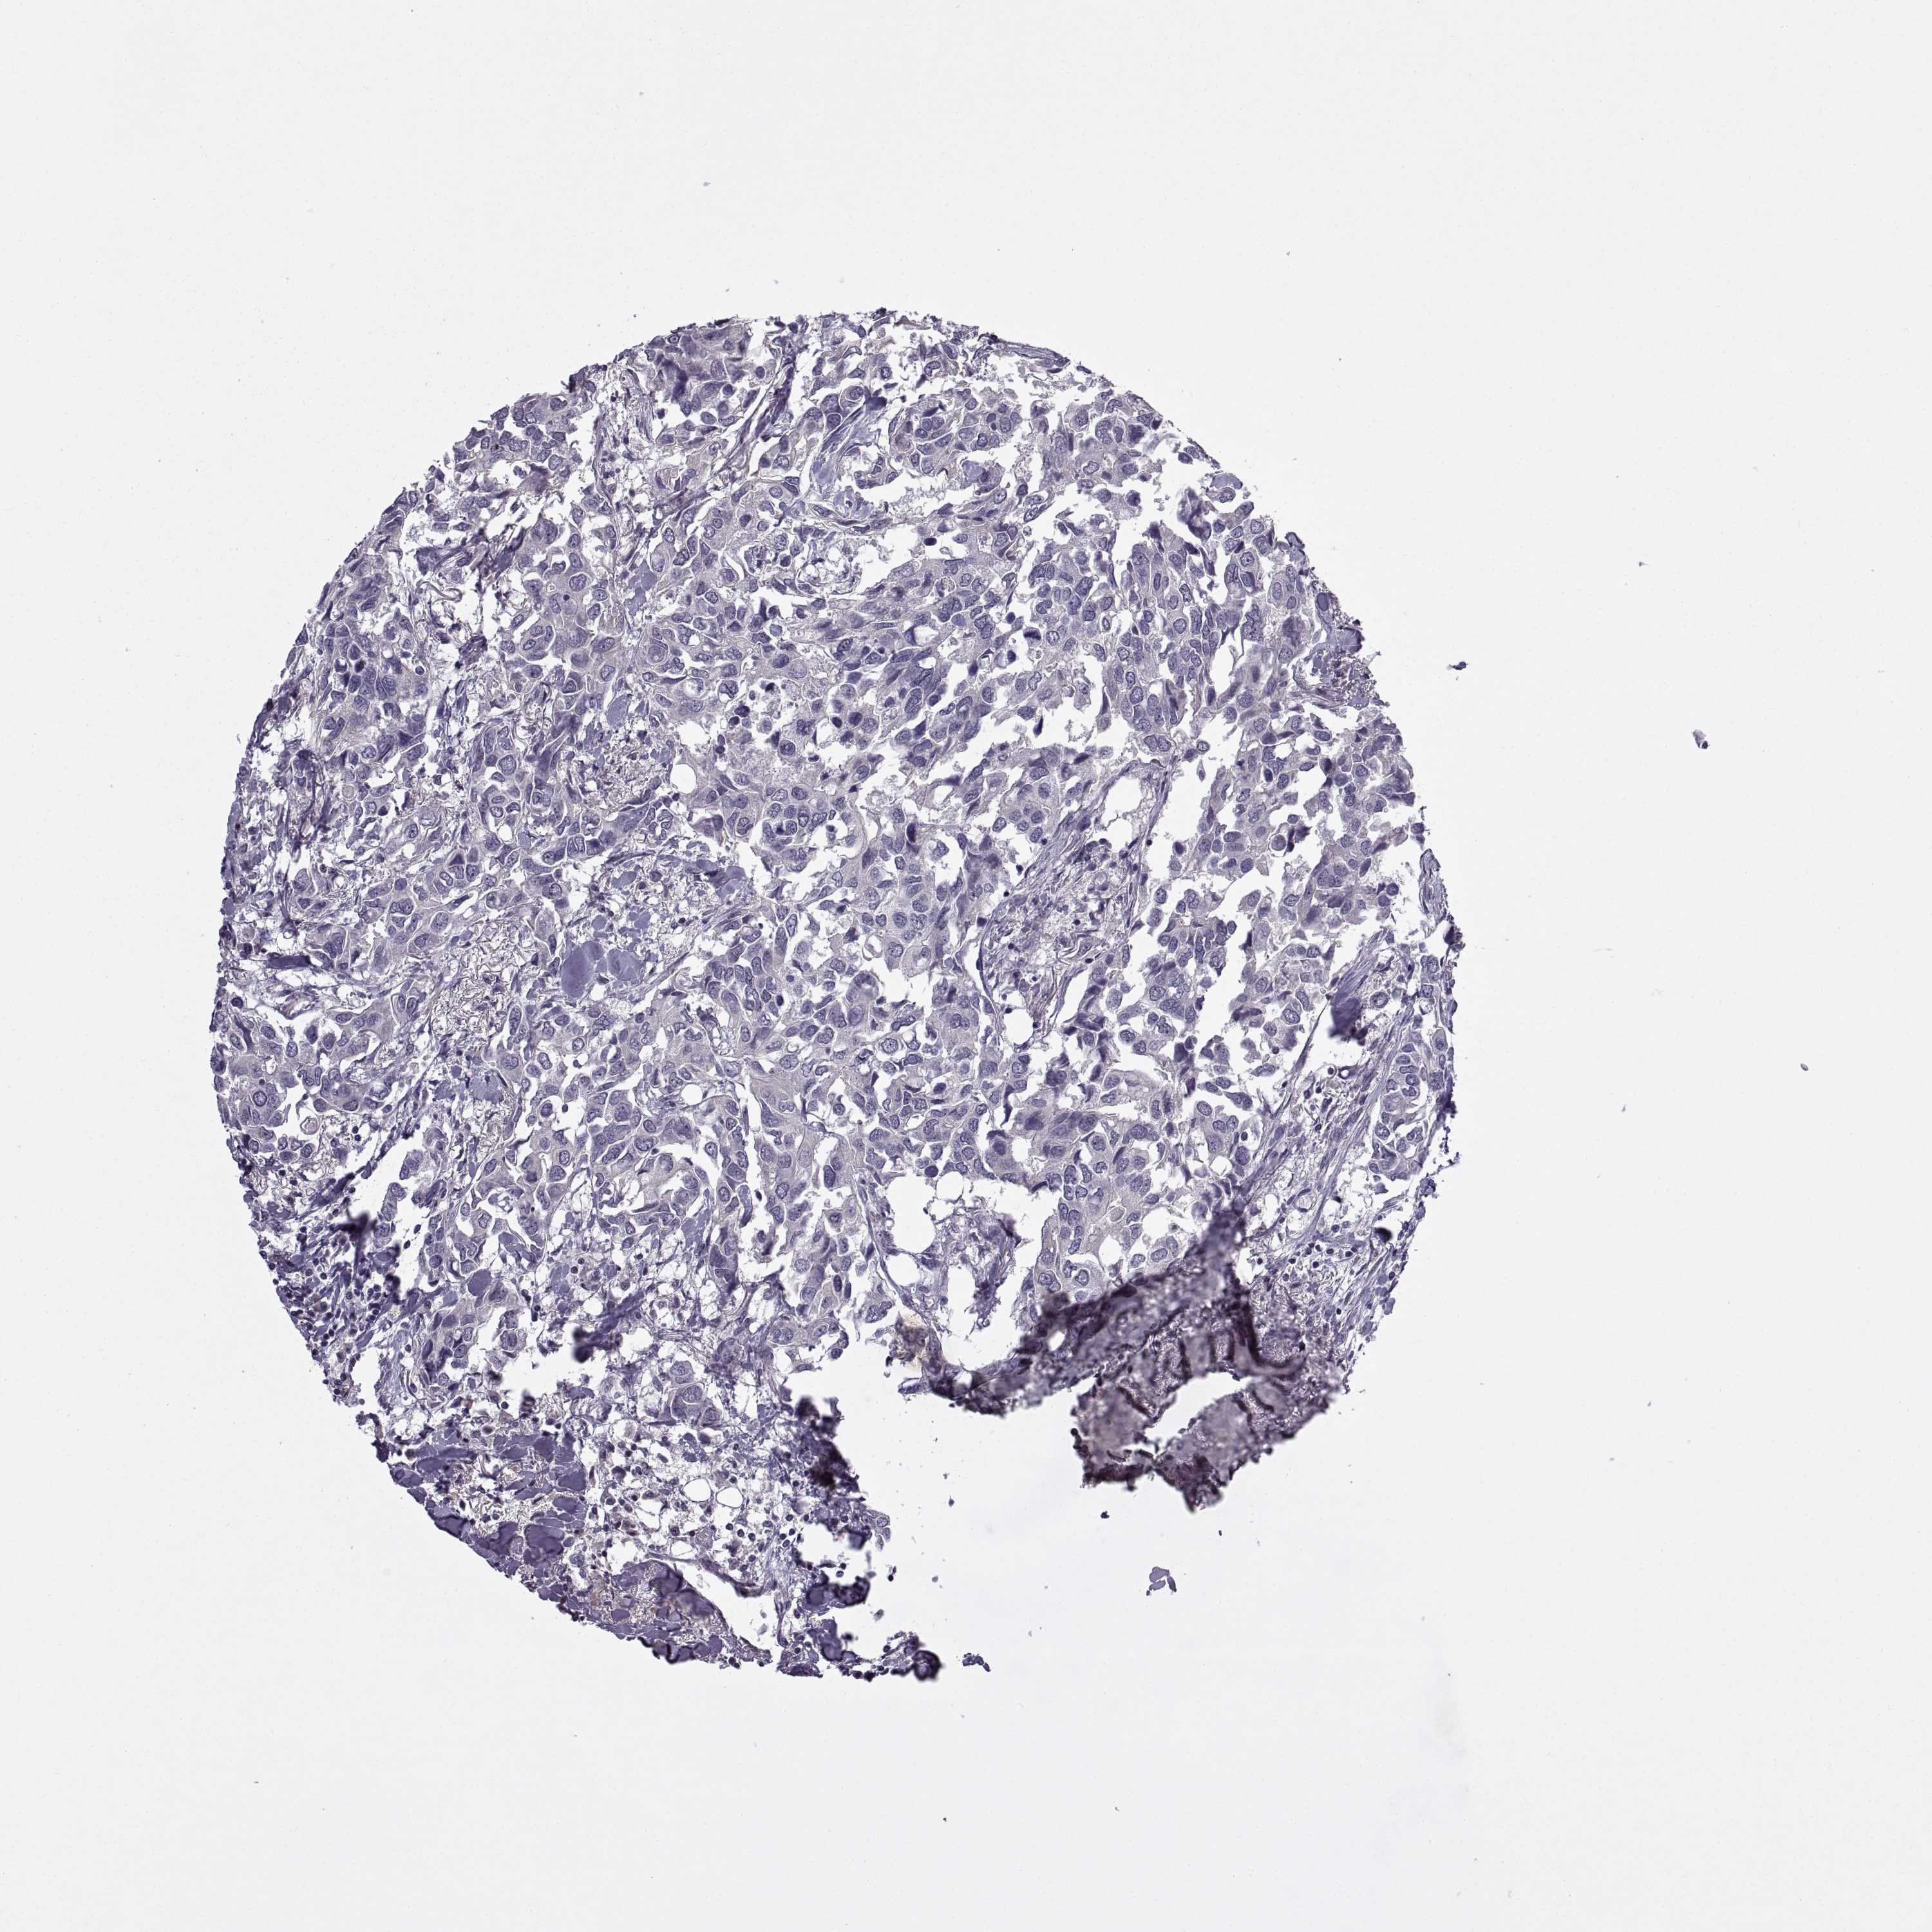

CANCER BREAST CANCER Show tissue menu

Breast cancer

Human cancer